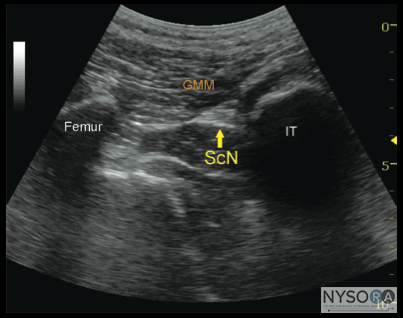

PART 2: TRANSGLUTEAL AND SUBGLUTEAL APPROACH ![]() Figure 2-1: Transsectional anatomy of the sciatic nerve at the transgluteal level. Sciatic nerve (ScN) is seen between the greater trochanter of the femur and the ischium tuberosity, just below the gluteus maximus (GMM) muscle.

FIgure 2-2: An ultrasound image demonstrating the sonoanatomy of the sciatic nerve (ScN). The ScN often assumes an ovoid or triangular shape and it is positioned underneath the gluteus muscle (GMM) between the ischium tuberosity (IT) and femur. General Considerations The use of ultrasonographic guidance greatly expanded the options that practitioners have for accomplishing the block of the sciatic nerve because the nerve can be imaged at several convenient levels. With the transgluteal approach, the needle is inserted just distal deep to the gluteus maximus muscle to reach the sciatic nerve. The sciatic nerve at the gluteal crease is readily identified in a predictable anatomic arrangement, between two osseous landmarks (ischial tuberosity and the greater trochanter) and beneath a well-defined muscle plane. The use of ultrasound visualization decreases the need for the geometry and measurements that are required for the classic landmark-based approaches. With the subgluteal approach, the nerve simply reached a few centimeters distally, just below the level of the subgluteal crease where imaging is not interfered by the bones. The preference of one approach over the other is made based on the patient's anatomic characteristics and personal preference. Ultrasound Anatomy At this transgluteal level, the sciatic nerve is visualized in the short axis between the two hyperechoic bony prominences of the ischial tuberosity and the greater trochanter of the femur (Figure 2-1 and 2-2). The gluteus maximus muscle is seen as the most superficial muscular layer bridging the two osseous structures, typically several centimeters thick. The sciatic nerve is located immediately deep to the gluteus muscles, superficial to the quadratus femoris muscle. Often, it is slightly closer to the ischial tuberosity (medial) aspect than the greater trochanter (lateral). At this location in the thigh, it is seen as an oval or roughly triangular hyperechoic structure. At the subgluteal level, however, the sciatic nerve is positioned deep to the long head of the biceps muscle and the posterior surface of the adductor magnus.